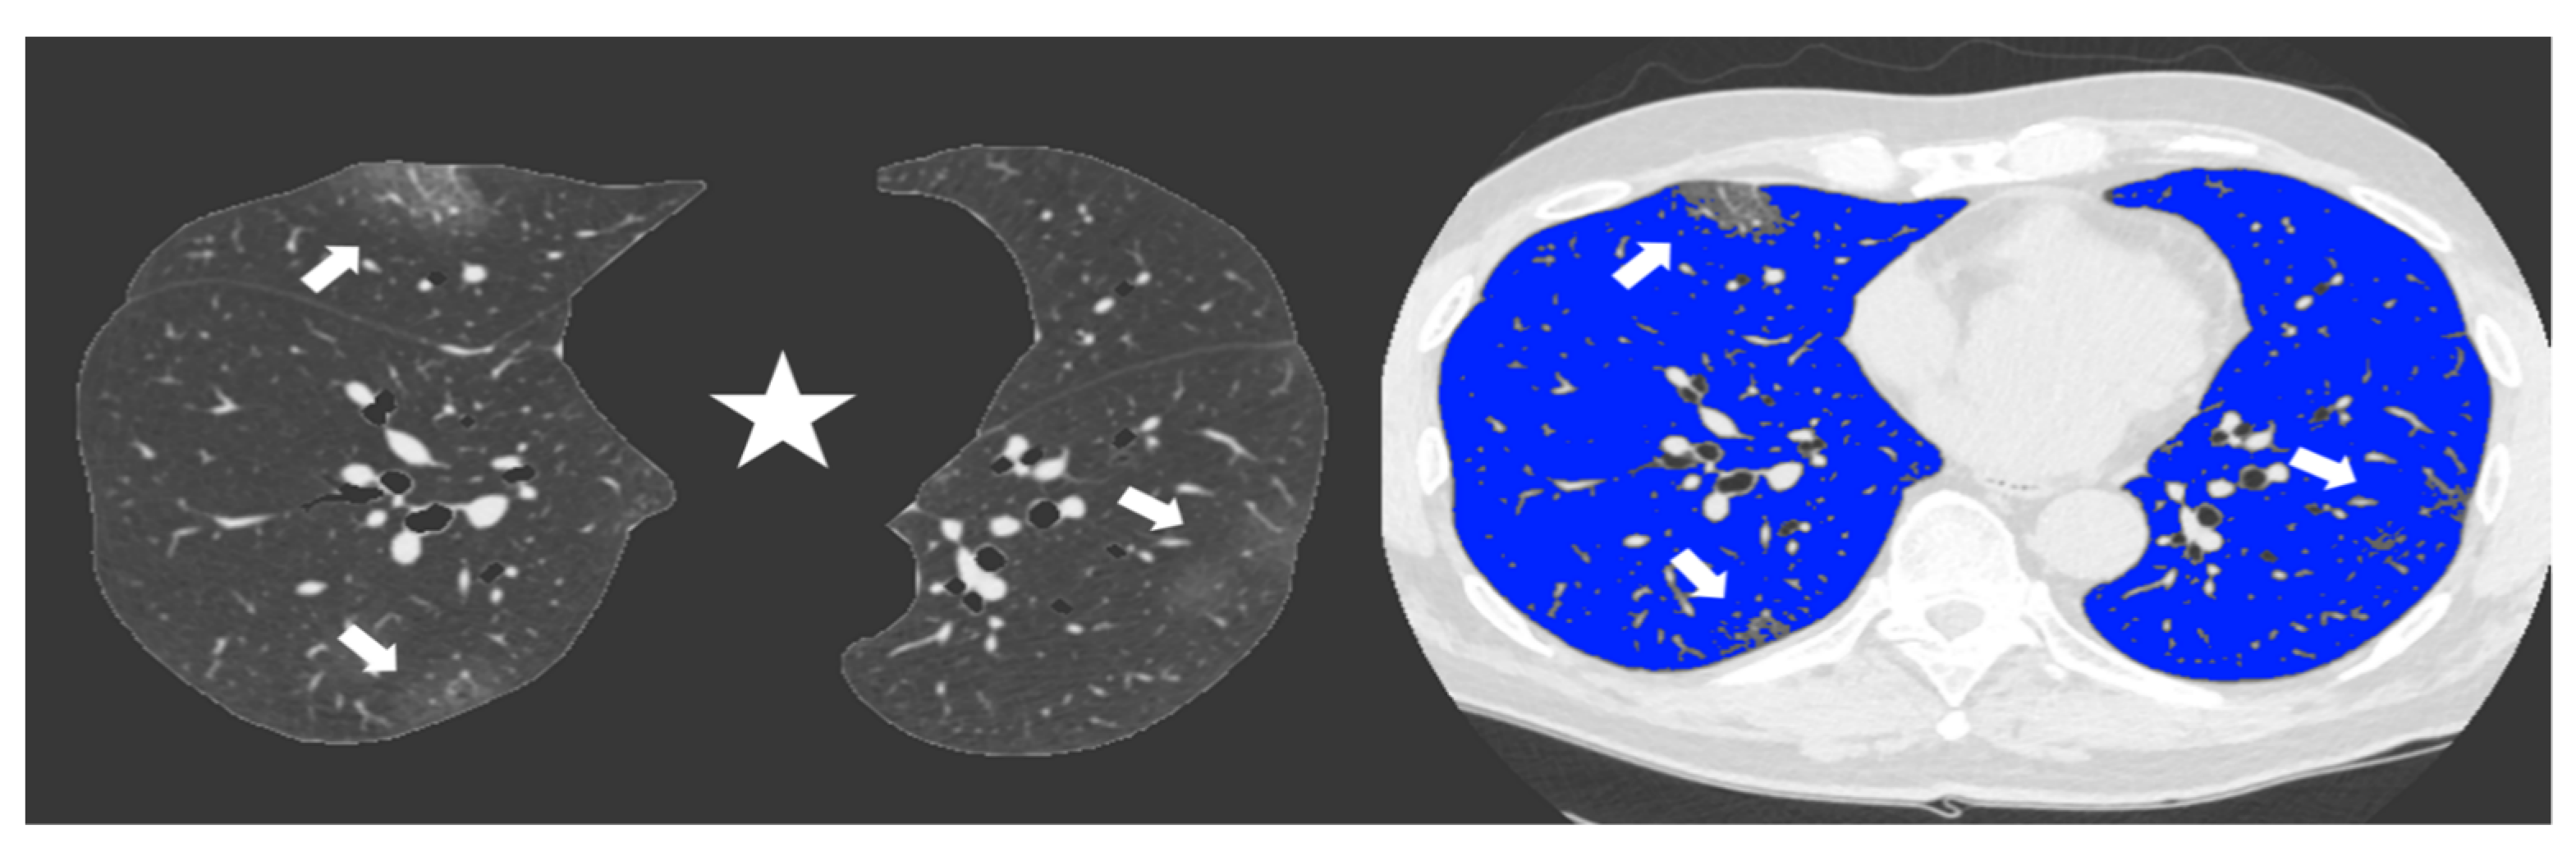

Since the beginning of the Covid-19 outbreak certain diagnosis of the disease was complicated by the multiplicity of symptoms and imaging features and due to the variability in the severity of disease at the time of presentation [1]. Chest CT has demonstrated an important role in predicting patients’ outcome because of the correlations between CT features and the severity of the disease [7,13]. In our study we demonstrated the correlation between the lung volume affected by the COVID-19 pneumonia and clinical outcome with a direct relationship between the infected lung percentage and the need for ventilation or subsequent death. Figure 2 and Figure 3 show lung volume analysis with dedicated software in comparison with standard CT images.

Figure 3. Non-enhanced axial Chest CT software reconstructions showing peripheral sub-pleural isolated GGOs (arrows). On the left the axial image automatically segmented by the software excluding all “non-lung” structures (mediastinum, upper airways and spine) (star) for visual quantification of infected parenchyma. On the right the same image highlighting in blue the well aerated lung and the COVID19 infection signs in grey. The whole infected volume assessed by software was 7% of the entire lung volume. The patient had good clinical course without need for invasive ventilation.